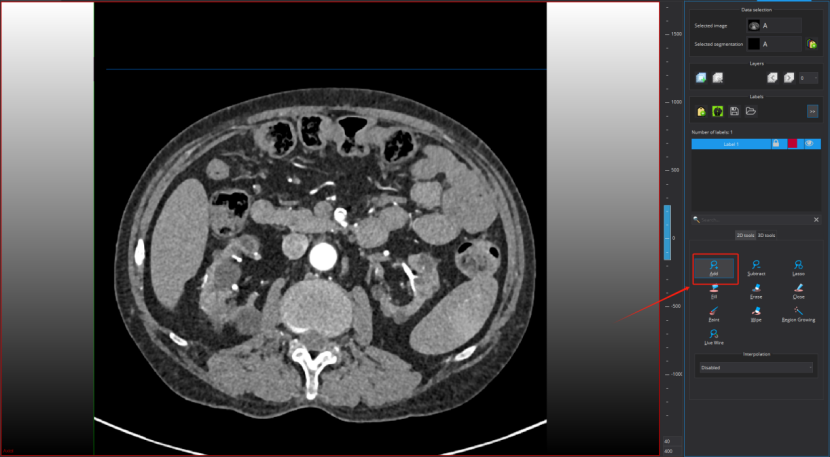

Step 1:点击标注工具add